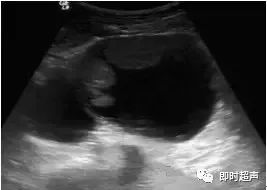

小婷繼續(xù)問道:醫(yī)生,左卵巢卵黃囊瘤伴巧克力囊腫應(yīng)該怎么預(yù)防呢?雌激素水平失調(diào):卵巢內(nèi)分泌調(diào)節(jié)混亂,雌激素分泌過剩,使卵巢內(nèi)的卵泡不能正常發(fā)育,從而形成卵黃囊瘤。...